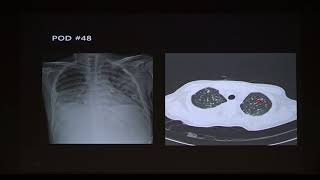

[연구발표] Comparison of conventional dose versus low-dose ganciclovir for cytomegalovirus prophylaxis after heart transplantation. 외 10편 + 더보기